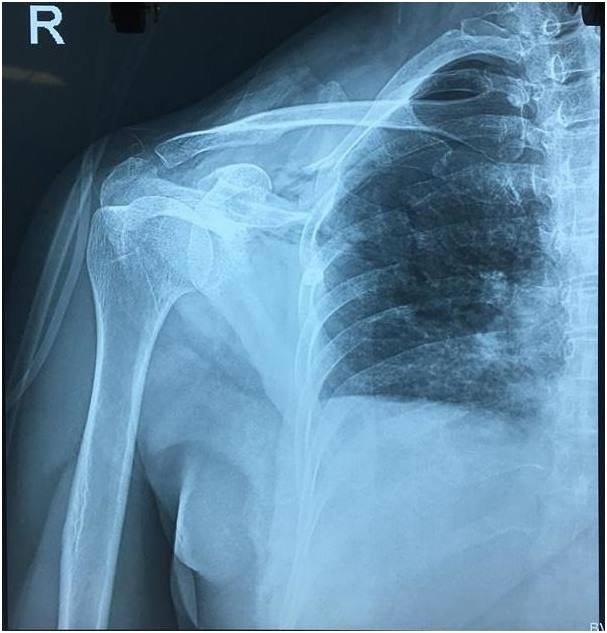

Qua thăm khám và các xét nghiệm, bệnh nhân được bác sĩ chẩn đoán đa chấn thương, sốc mất máu, suy hô hấp tràn máu tràn khí màng phổi bên phải do vết thương thấu ngực. Đặc biệt, bệnh nhân có nhóm máu hiếm -O Rh(-), buộc các bác sĩ phải cân nhắc rất nhiều trong việc xử lý cấp cứu.

| Tổn thương của bệnh nhân N. khi vào viện. Ảnh: T.N. |